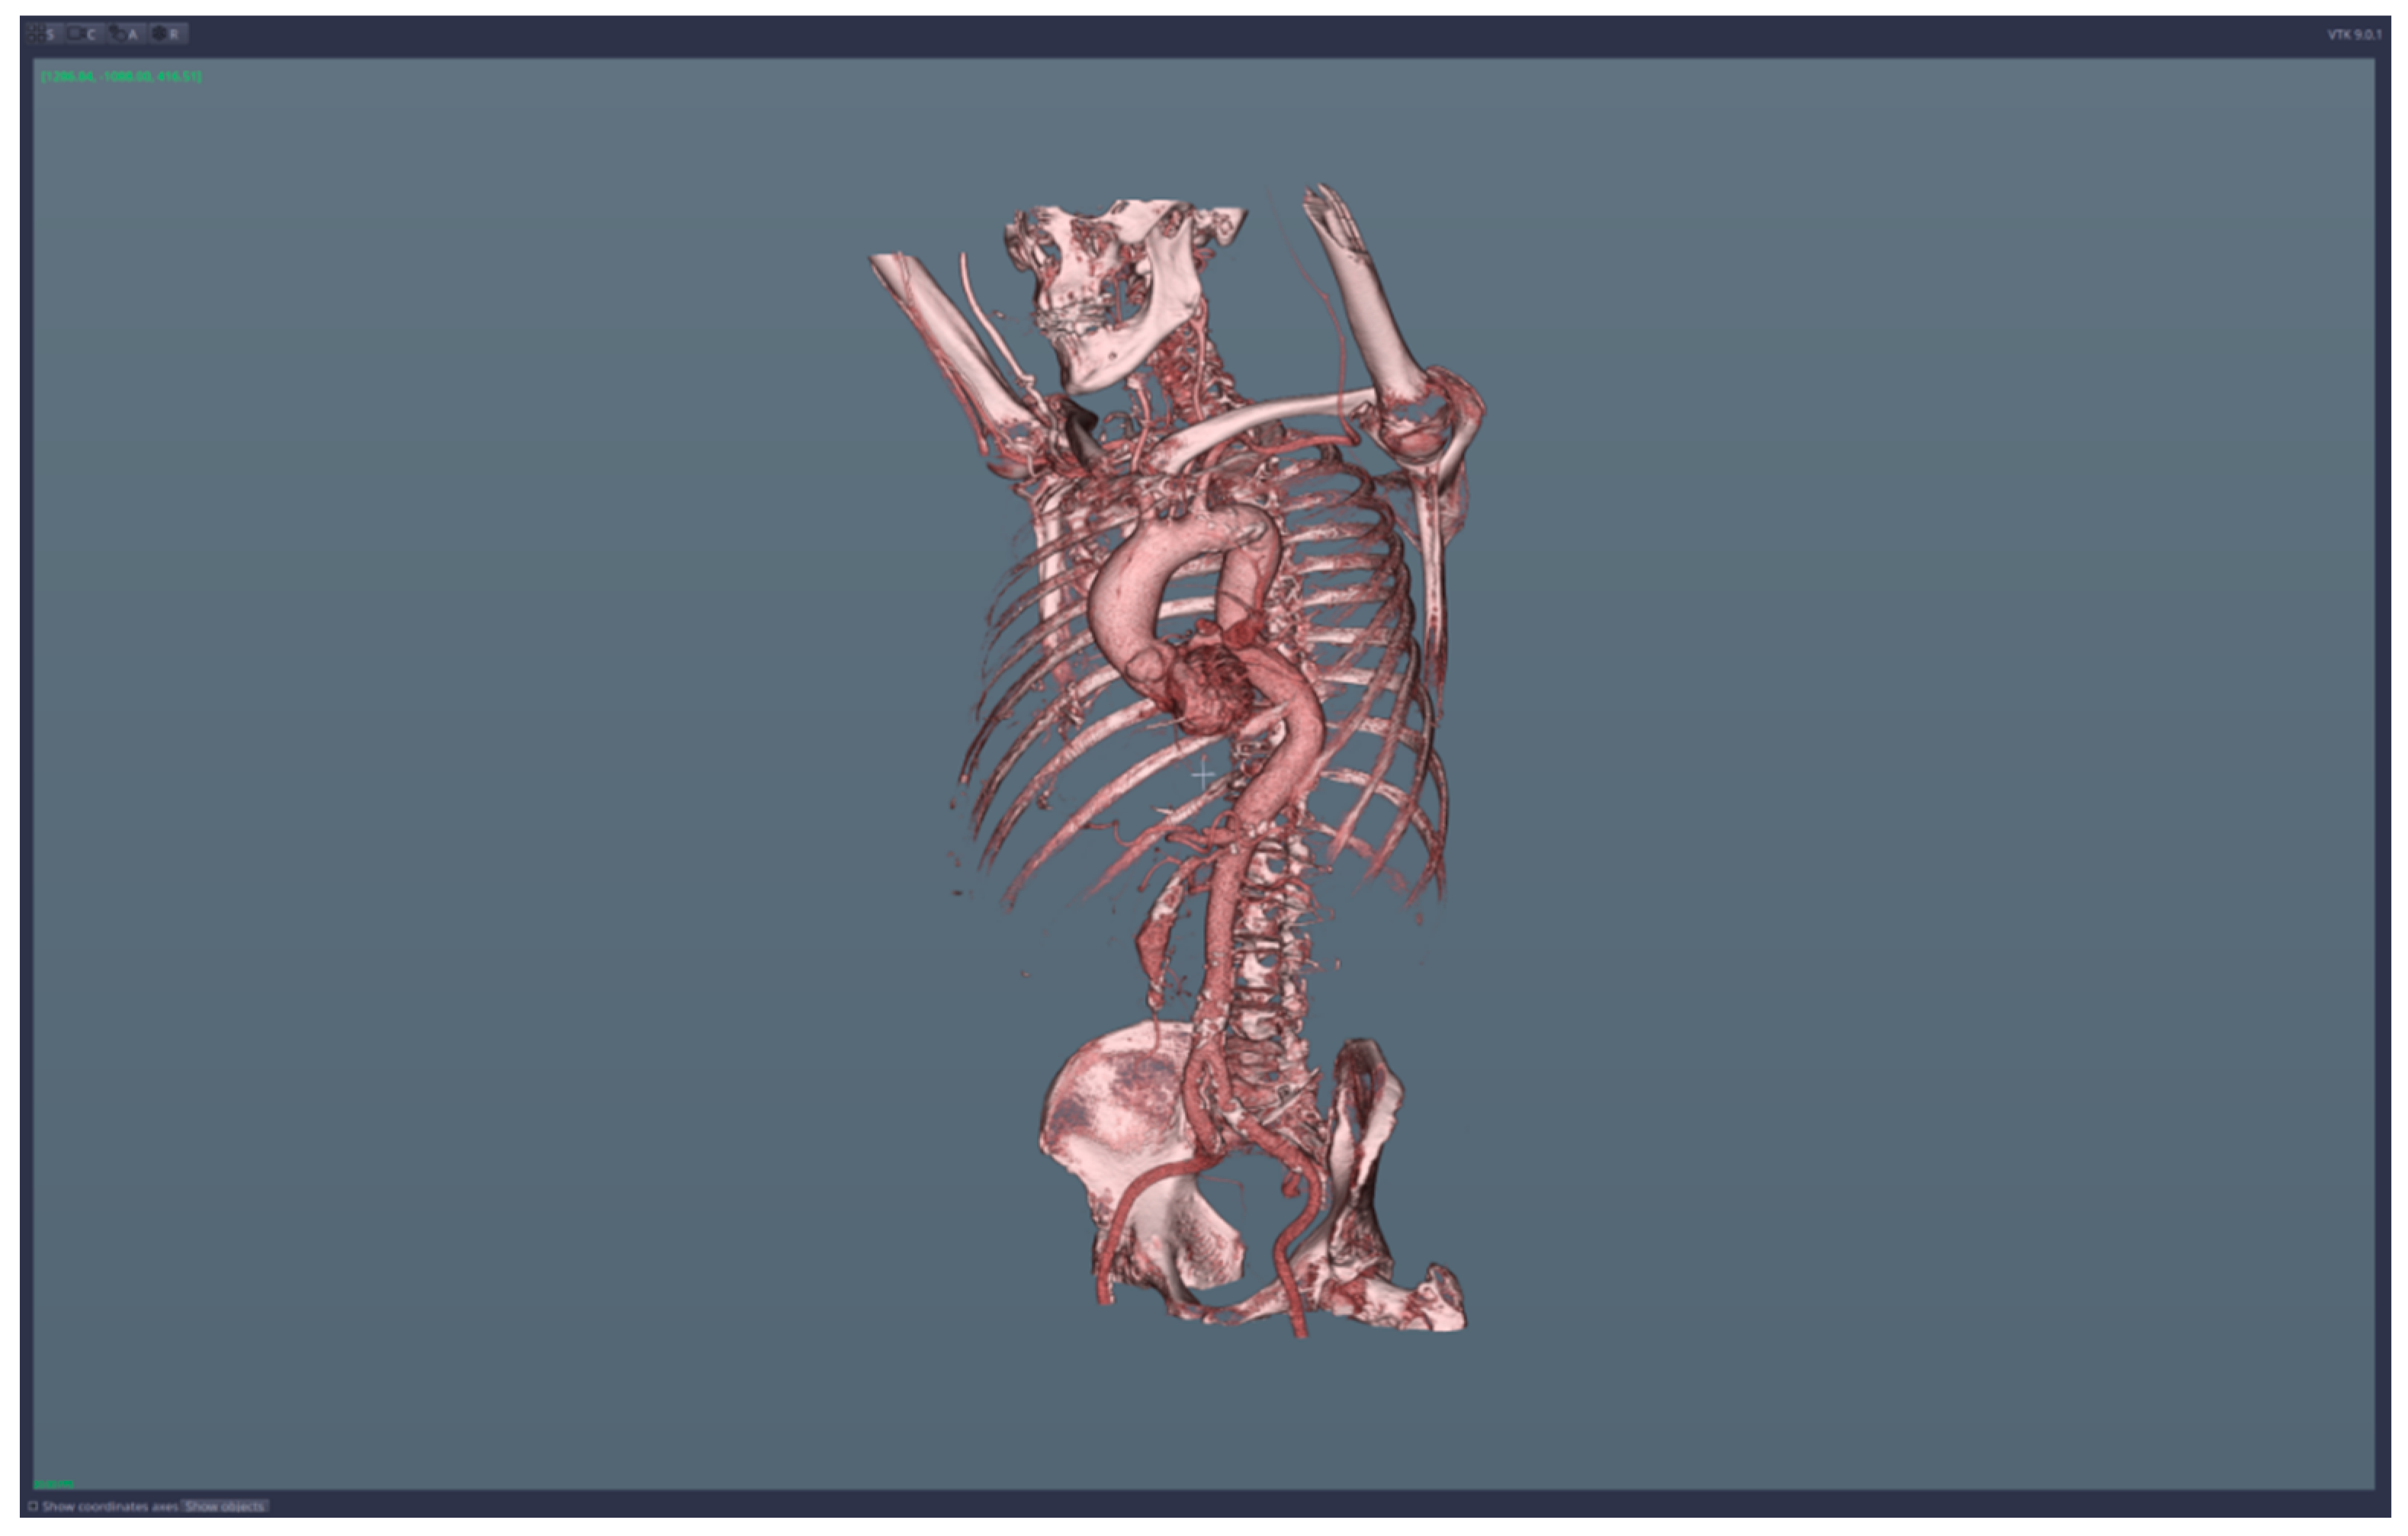

• 3D reconstruction and visualization of arteries (see Figure 1 and Figure 2)

We applied the suggested pre-operatory planning procedure on CT data from a male patient aged 74. The scans were performed using a Siemens Somatom go. Top 128 slice machine [18], with contrast substance (ULTRAVIST 370 I.V.). The series used for planning took 647 slices at a distance of 0.99 mm each. The reconstructed 3D image had 655 × 512 × 647 voxels.

Figure 1. Images of the 3D CT reconstruction and 2D sections.

Figure 2. Images of the 3D reconstruction of main arteries and mesenteric artery aneurysm.